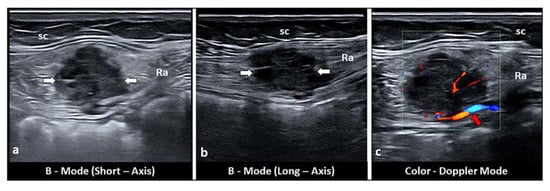

- Savelli, L.; Manuzzi, L.; Di Donato, N.; Salfi, N.; Trivella, G.; Ceccaroni, M.; Seracchioli, R. Endometriosis of the abdominal wall: Ultrasonographic and Doppler characteristics. Ultrasound Obstet. Gynecol. 2012, 39, 336–340. [Google Scholar] [CrossRef]